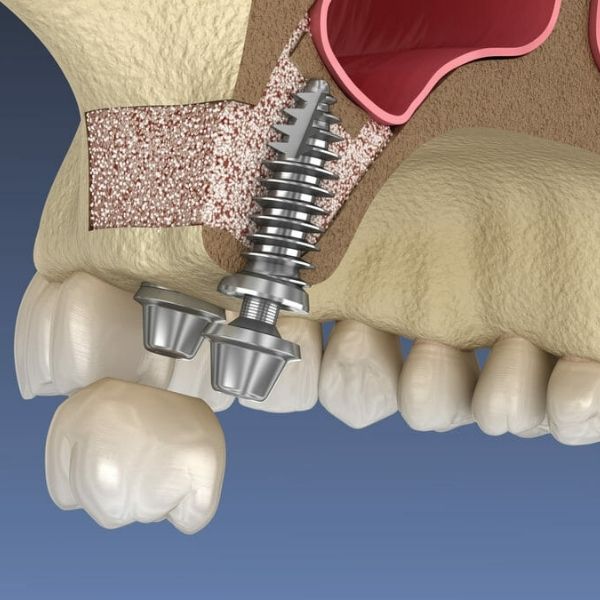

A sinus lift (sinus augmentation) raises the sinus membrane upward and places bone graft material underneath. This creates the foundation needed for implants to integrate securely. Our surgical team uses advanced 3D imaging and careful technique to safely lift the sinus membrane without perforation, ensuring optimal bone augmentation for long-term implant success.

Lateral Window Technique: Used for significant bone augmentation needs. We create a small window in the lateral wall of the maxillary sinus, gently lift the sinus membrane, and place bone graft material in the created space. This technique allows for substantial height gain—often 8-10mm or more. The procedure typically takes 1-2 hours and requires 4-6 months of healing before implant placement.

The sinus membrane (Schneiderian membrane) is gently lifted away from the sinus floor using specialized instruments. Extreme care is taken to prevent perforation.

Bone graft material is carefully packed into the space created beneath the elevated membrane, building the height needed for future implant placement.